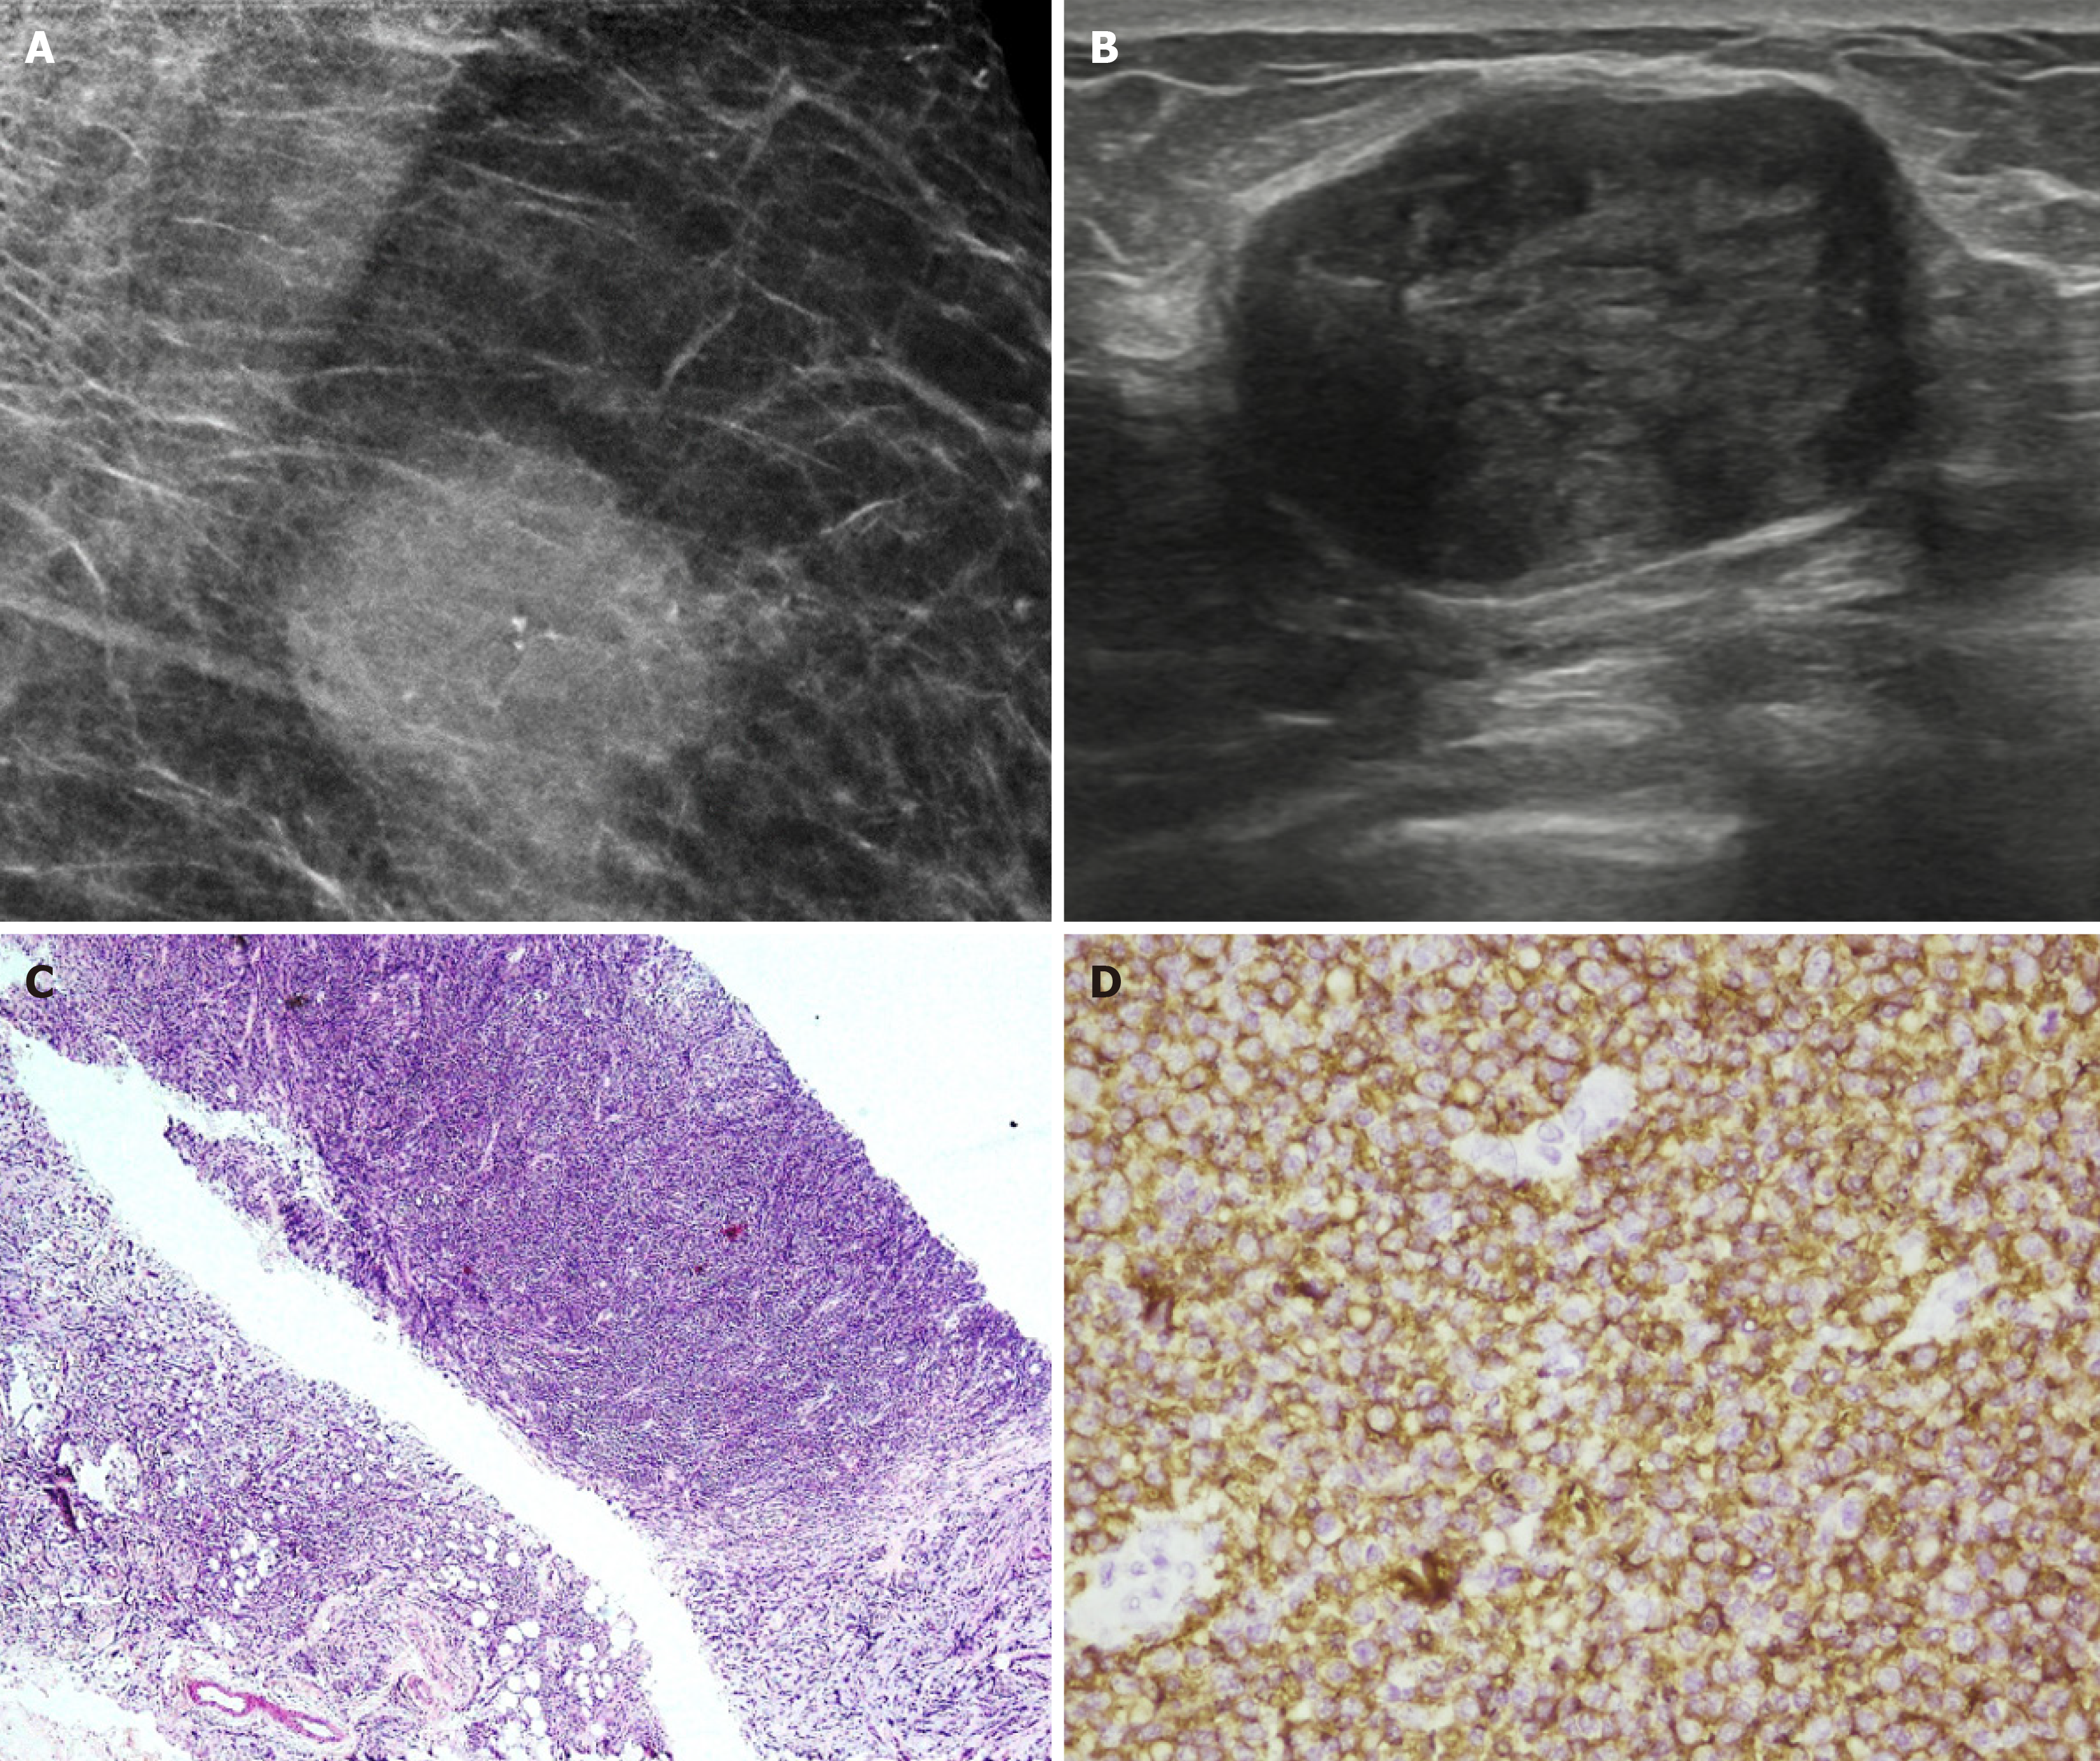

Figure 20  Invasive lobular carcinoma in a 65-year-old male with a hard retroareolar lump.

A: Mediolateral oblique; B: Craniocaudal mammography views showing an irregular high-density mass with spiculated margins, few punctate calcific foci and surrounding architectural distortion. Nipple retraction and overlying skin thickening are also observed; C: Ultrasound; D: Elastography images show an irregular mass with angular margins, which appears hard on elastography; E: Histopathology (hematoxylin and eosin, × 40); F: E-cadherin images show medium to small dyscohesive cells that lack E-cadherin expression.